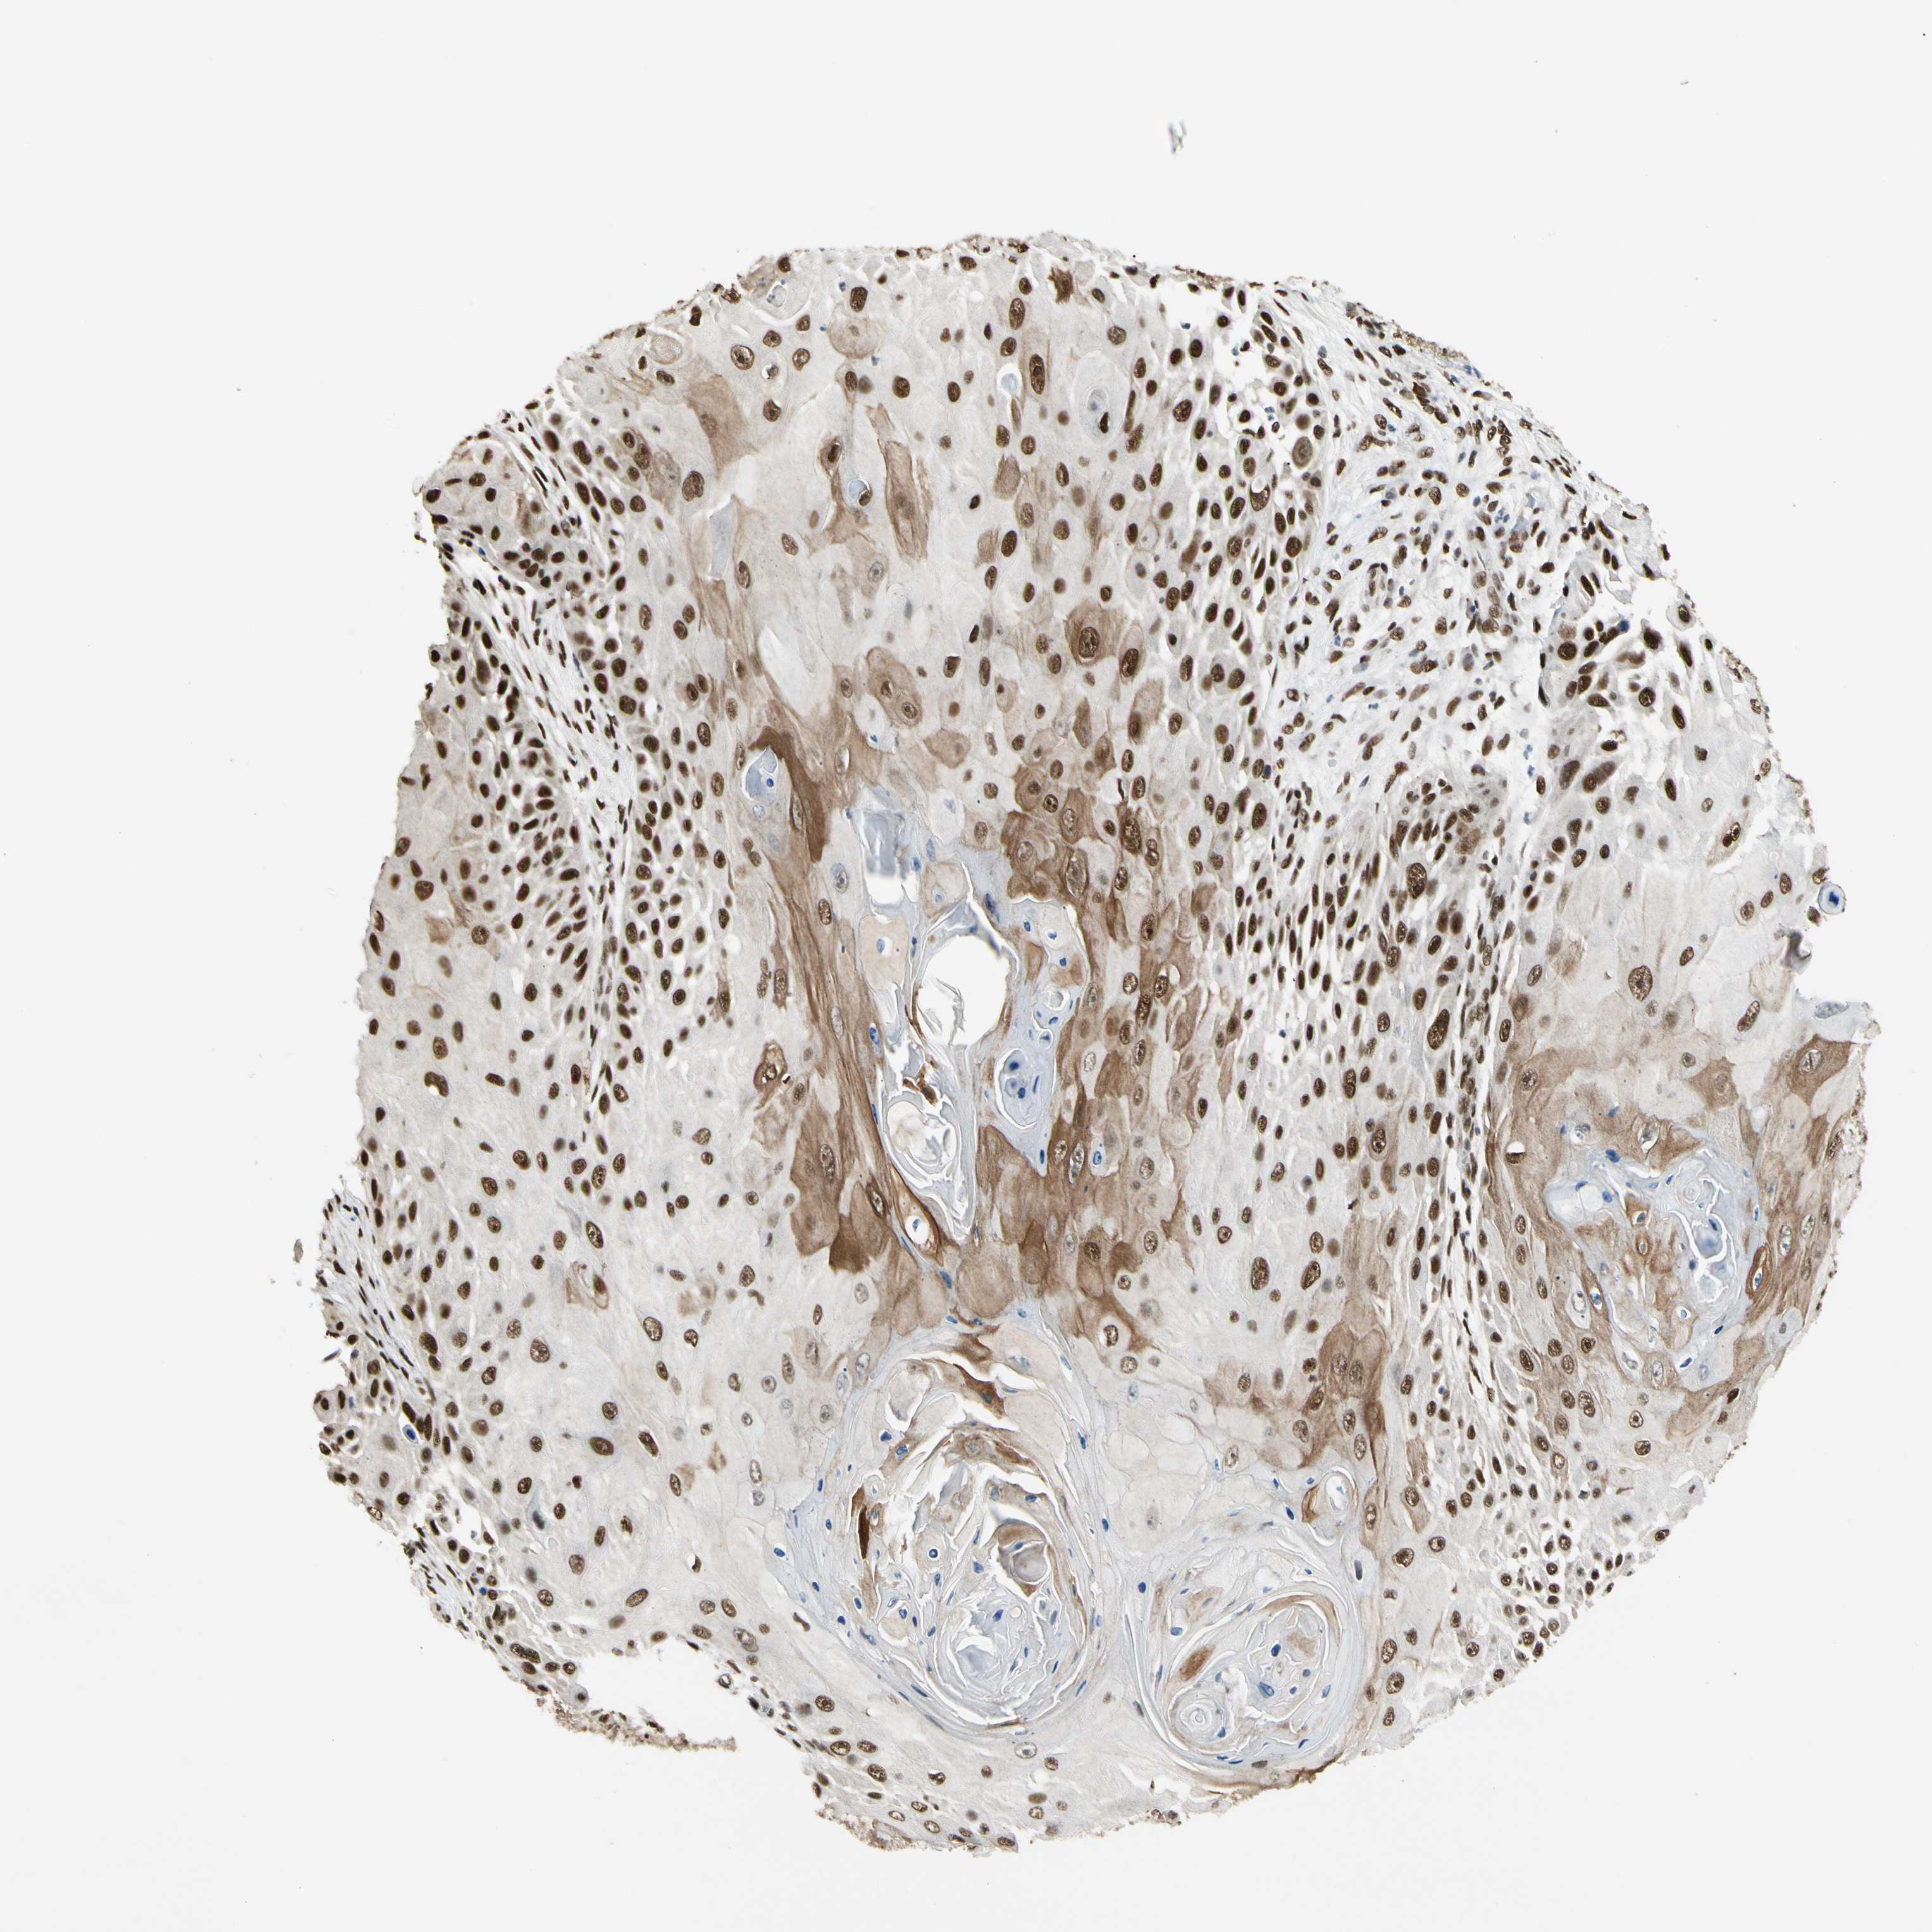

SKIN CANCER - Protein expressioni

A mouse-over function shows sample information and annotation data. Click on an image to view it in a full screen mode. Samples can be filtered based on level of antibody staining by selecting one or several of the following categories: high, medium, low and not detected. The assay and annotation is described here.

Antibody staining in the annotated cell types in the current human tissue is reported as not detected, low, medium, or high, based on conventional immunohistochemistry profiling in selected tissues. This score is based on the combination of the staining intensity and fraction of stained cells.

Each image is clickable and will lead to virtual microscopy that enables deeper exploration of all samples and also displays staining intensity scores, fraction scores and subcellular localization as well as patient and tissue information for each sample.

Antibody CAB058691

Staining

High

Medium

Low

Not detected

Intensity

Strong

Moderate

Weak

Negative

Quantity

>75%

75%-25%

<25%

None

Location

Nuclear

Cytoplasmic/membranous

Cytoplasmic/membranous,nuclear

Squamous cell carcinoma, NOS

Squamous cell carcinoma, metastatic, NOS

Basal cell carcinoma

Papilloma, NOS